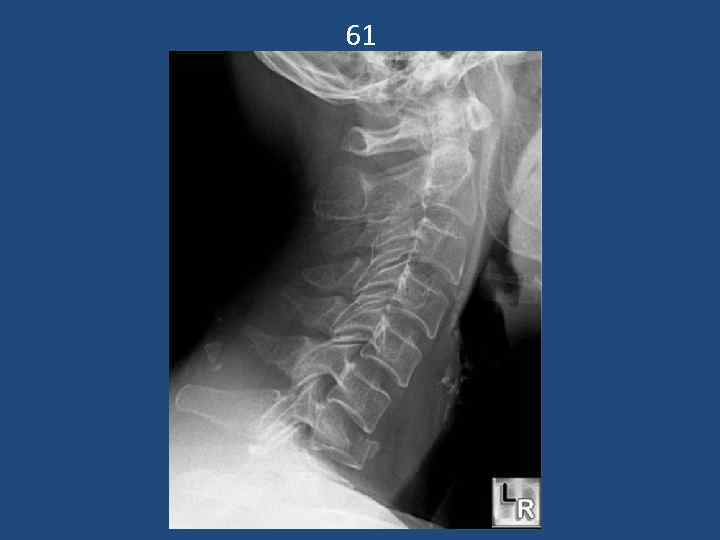

61

Подвывих с2 позвонка кпереди. Перелом остистого отростка с4. 51

52 Стабильный перелом края тела с7

13 Подвывих с3 кпереди. Взрывной перелом с6